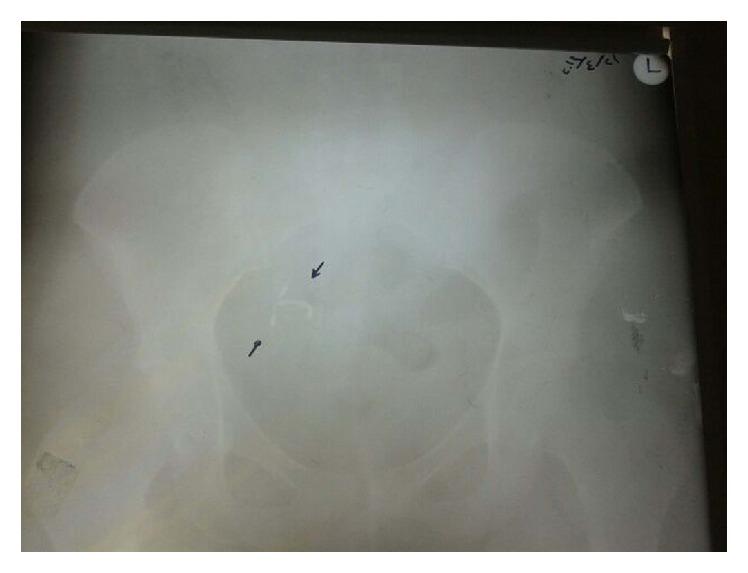

Intrauterine devices (IUDs) remain highly effective reversible family planning methods in developing countries. We aimed to report one of the complications of extrauterine and intrauterine devices. A 44-year-old woman was admitted to our hospital with mislocated intrauterine device and abnormal uterine bleeding. Extrauterine IUD device was proven by ultrasound and X-ray. She had normal blood test count with a negative pregnancy test. There are several cases of complications with intrauterine devices, but this is the first case report about an extrauterine IUD embedded by inflame enlarged appendix presenting with abnormal uterine bleeding. Although intrauterine devices are a common safe method for contraception, there is no risk-free insertion even with advanced ultrasounds. A regular self-examination should be taught to the patients and ultrasonography should be performed in the follow-up of the patients especially for inserted devices during lactation period. Extrauterine IUDs can be successfully removed by laparotomy.

宫内节育器(IUD)在发展中国家仍然是非常有效的可逆性计划生育方法。我们旨在报告一例宫内和宫外节育器的并发症。一名44岁女性因宫内节育器位置异常和子宫异常出血入院。超声和X线检查证实节育器位于宫外。她血常规正常,妊娠试验阴性。宫内节育器有多种并发症病例,但这是首例关于宫外节育器嵌入发炎肿大阑尾并伴有子宫异常出血的病例报告。尽管宫内节育器是一种常用的安全避孕方法,但即使使用先进的超声检查,也并非无风险置入。应教会患者定期自我检查,尤其是哺乳期置入节育器的患者,随访时应进行超声检查。宫外节育器可通过剖腹手术成功取出。